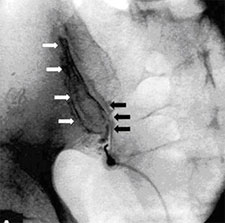

S'observa l'agulla a l'entrada de l'articulació sacroilíaca. En blanc, s'assenyala el marge lateral de la part anterior de l'articulació. Les fletxes negres posen de manifest el marge medial de la part posterior de l'articulació després d'injectar el contrast.